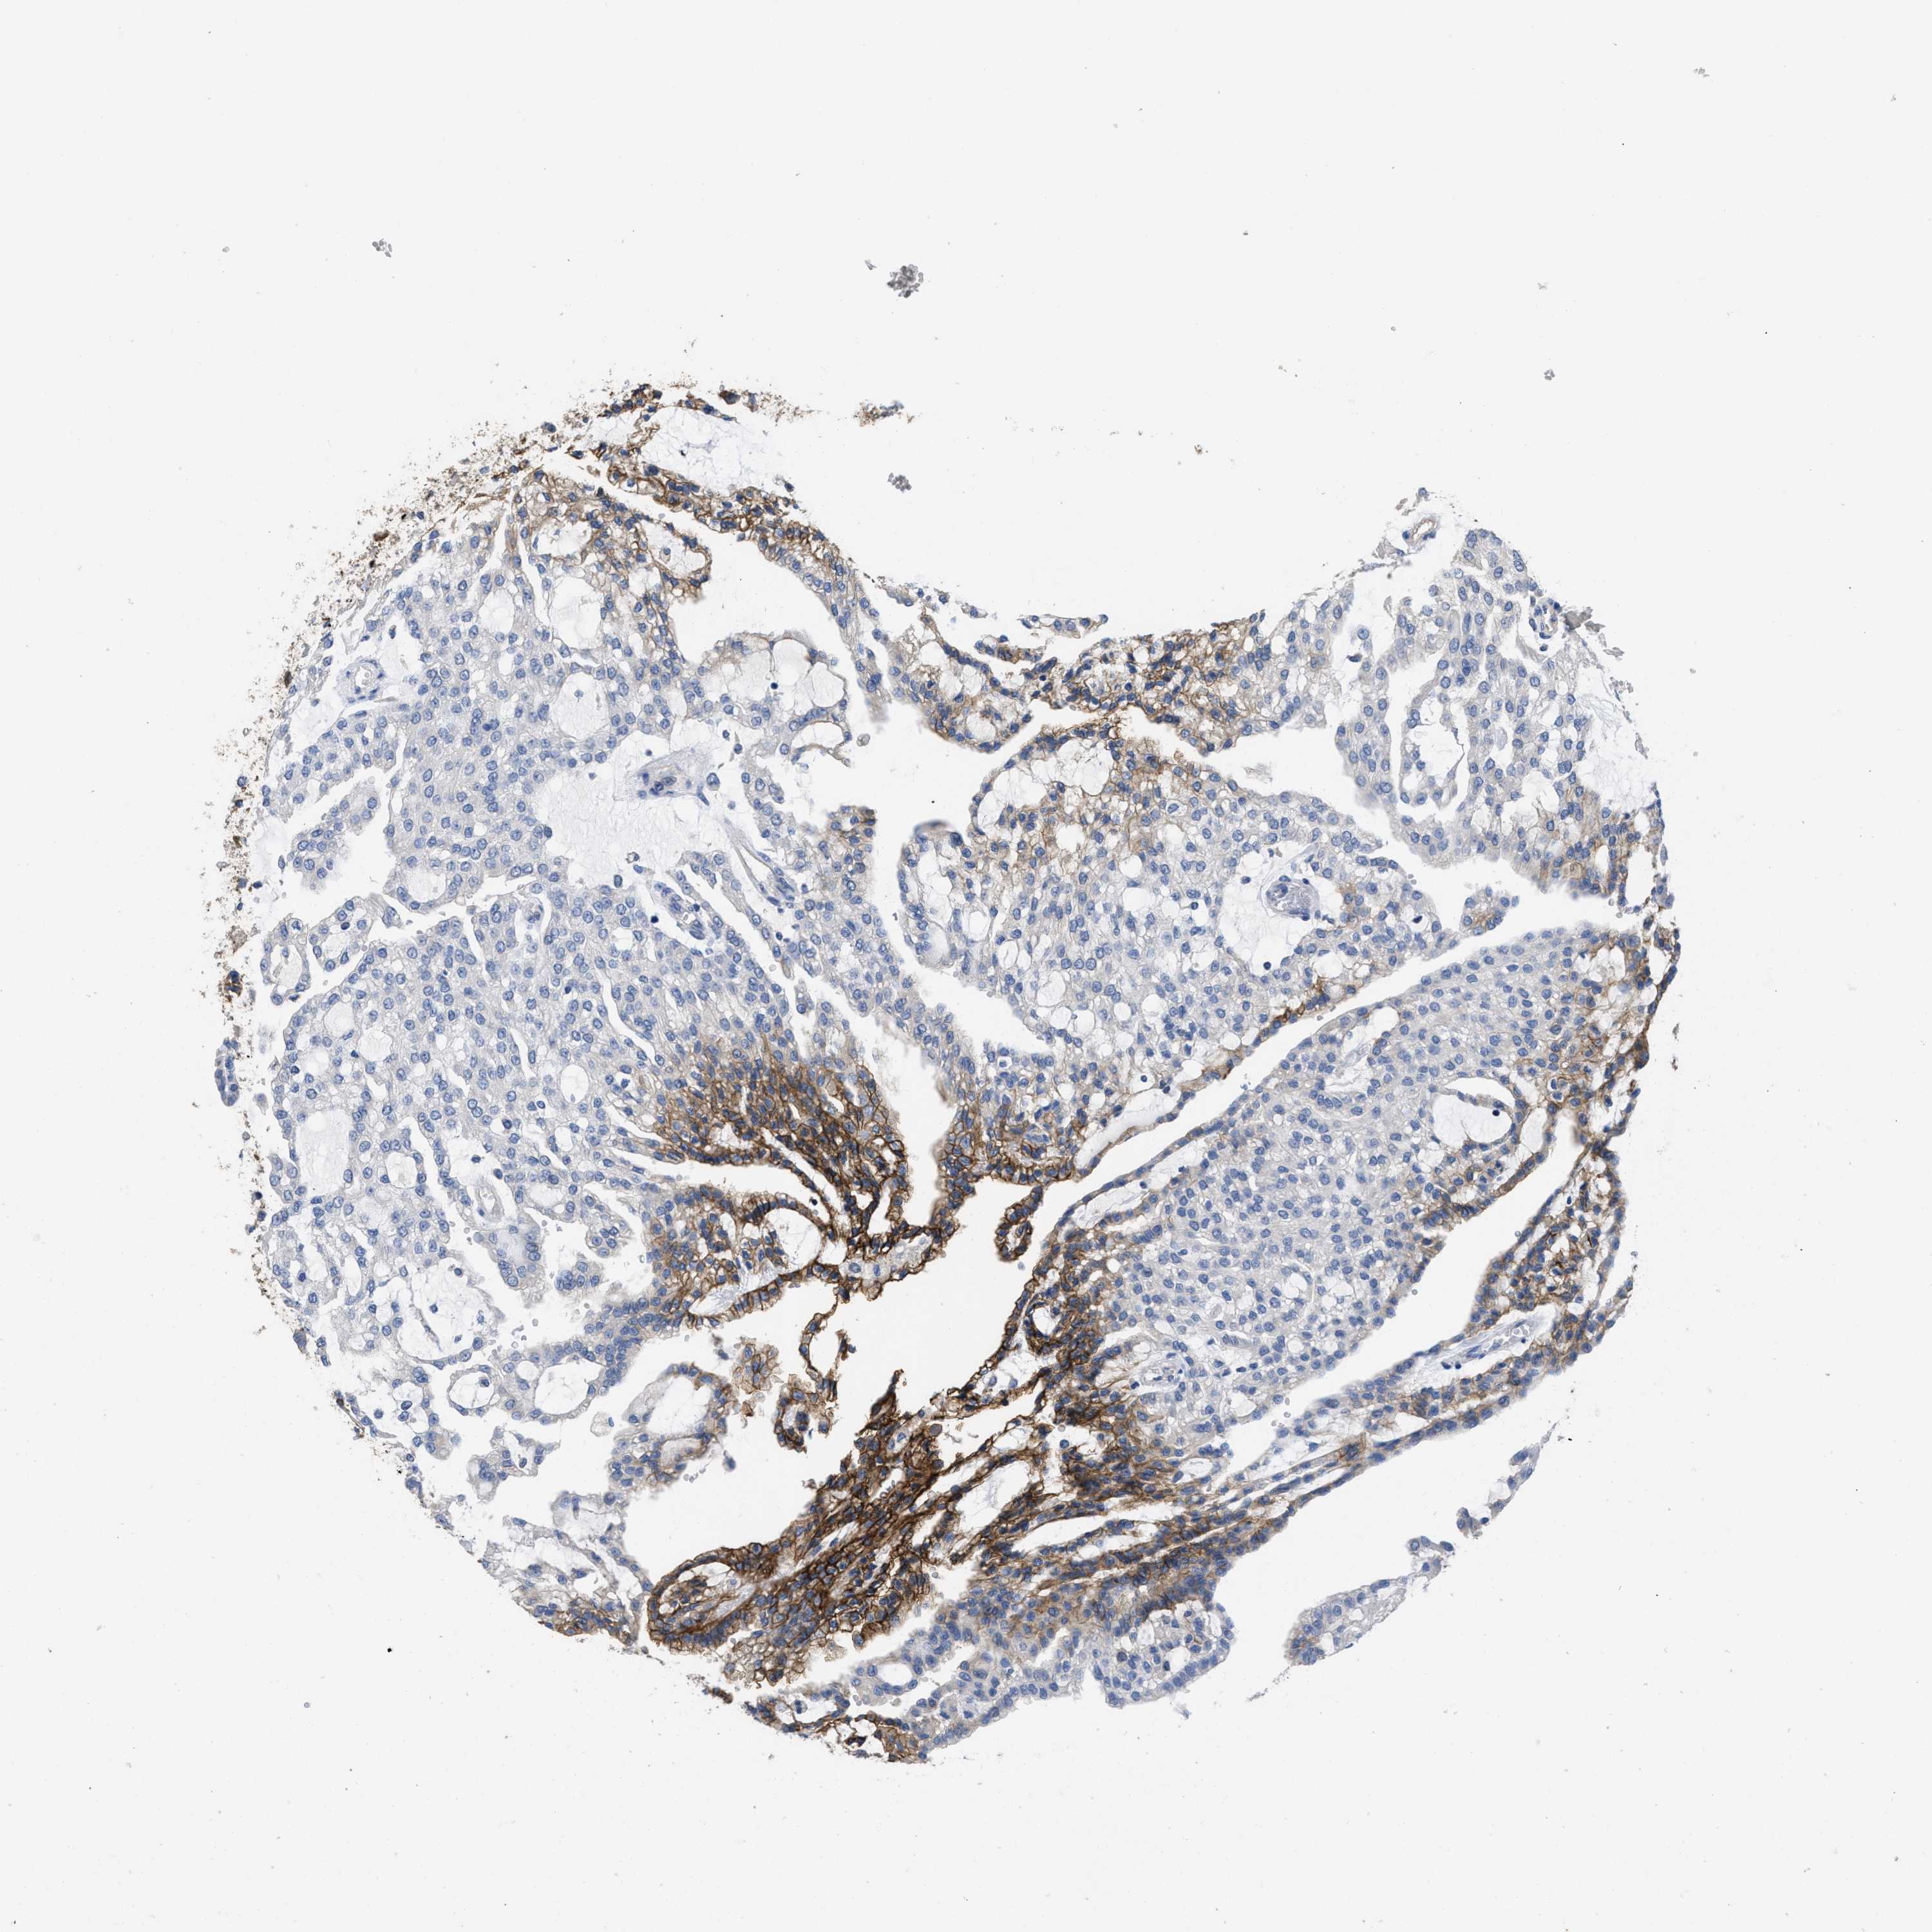

CANCER RENAL CANCER Show tissue menu

KICH TCGA KIRC TCGA KIRC VALIDATION KIRP TCGA PROTEIN RCC CPTAC PROTEIN EXPRESSION